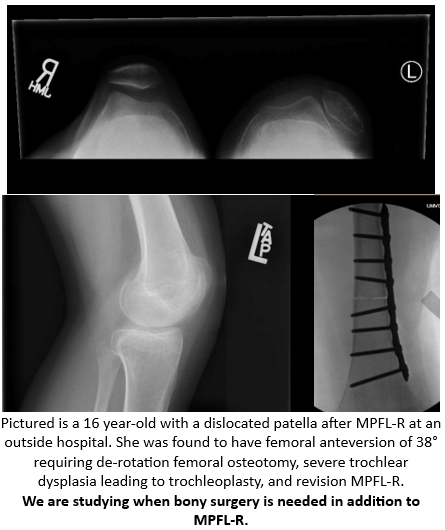

The JUPITER Study - JUPITER 4.0 - Risk Factors for Failure of Isolated Medial Patellofemoral Ligament Reconstruction - can now be found on ClinicalTrials.gov! See study record here: clinicaltrials.gov/study/NCT06883…